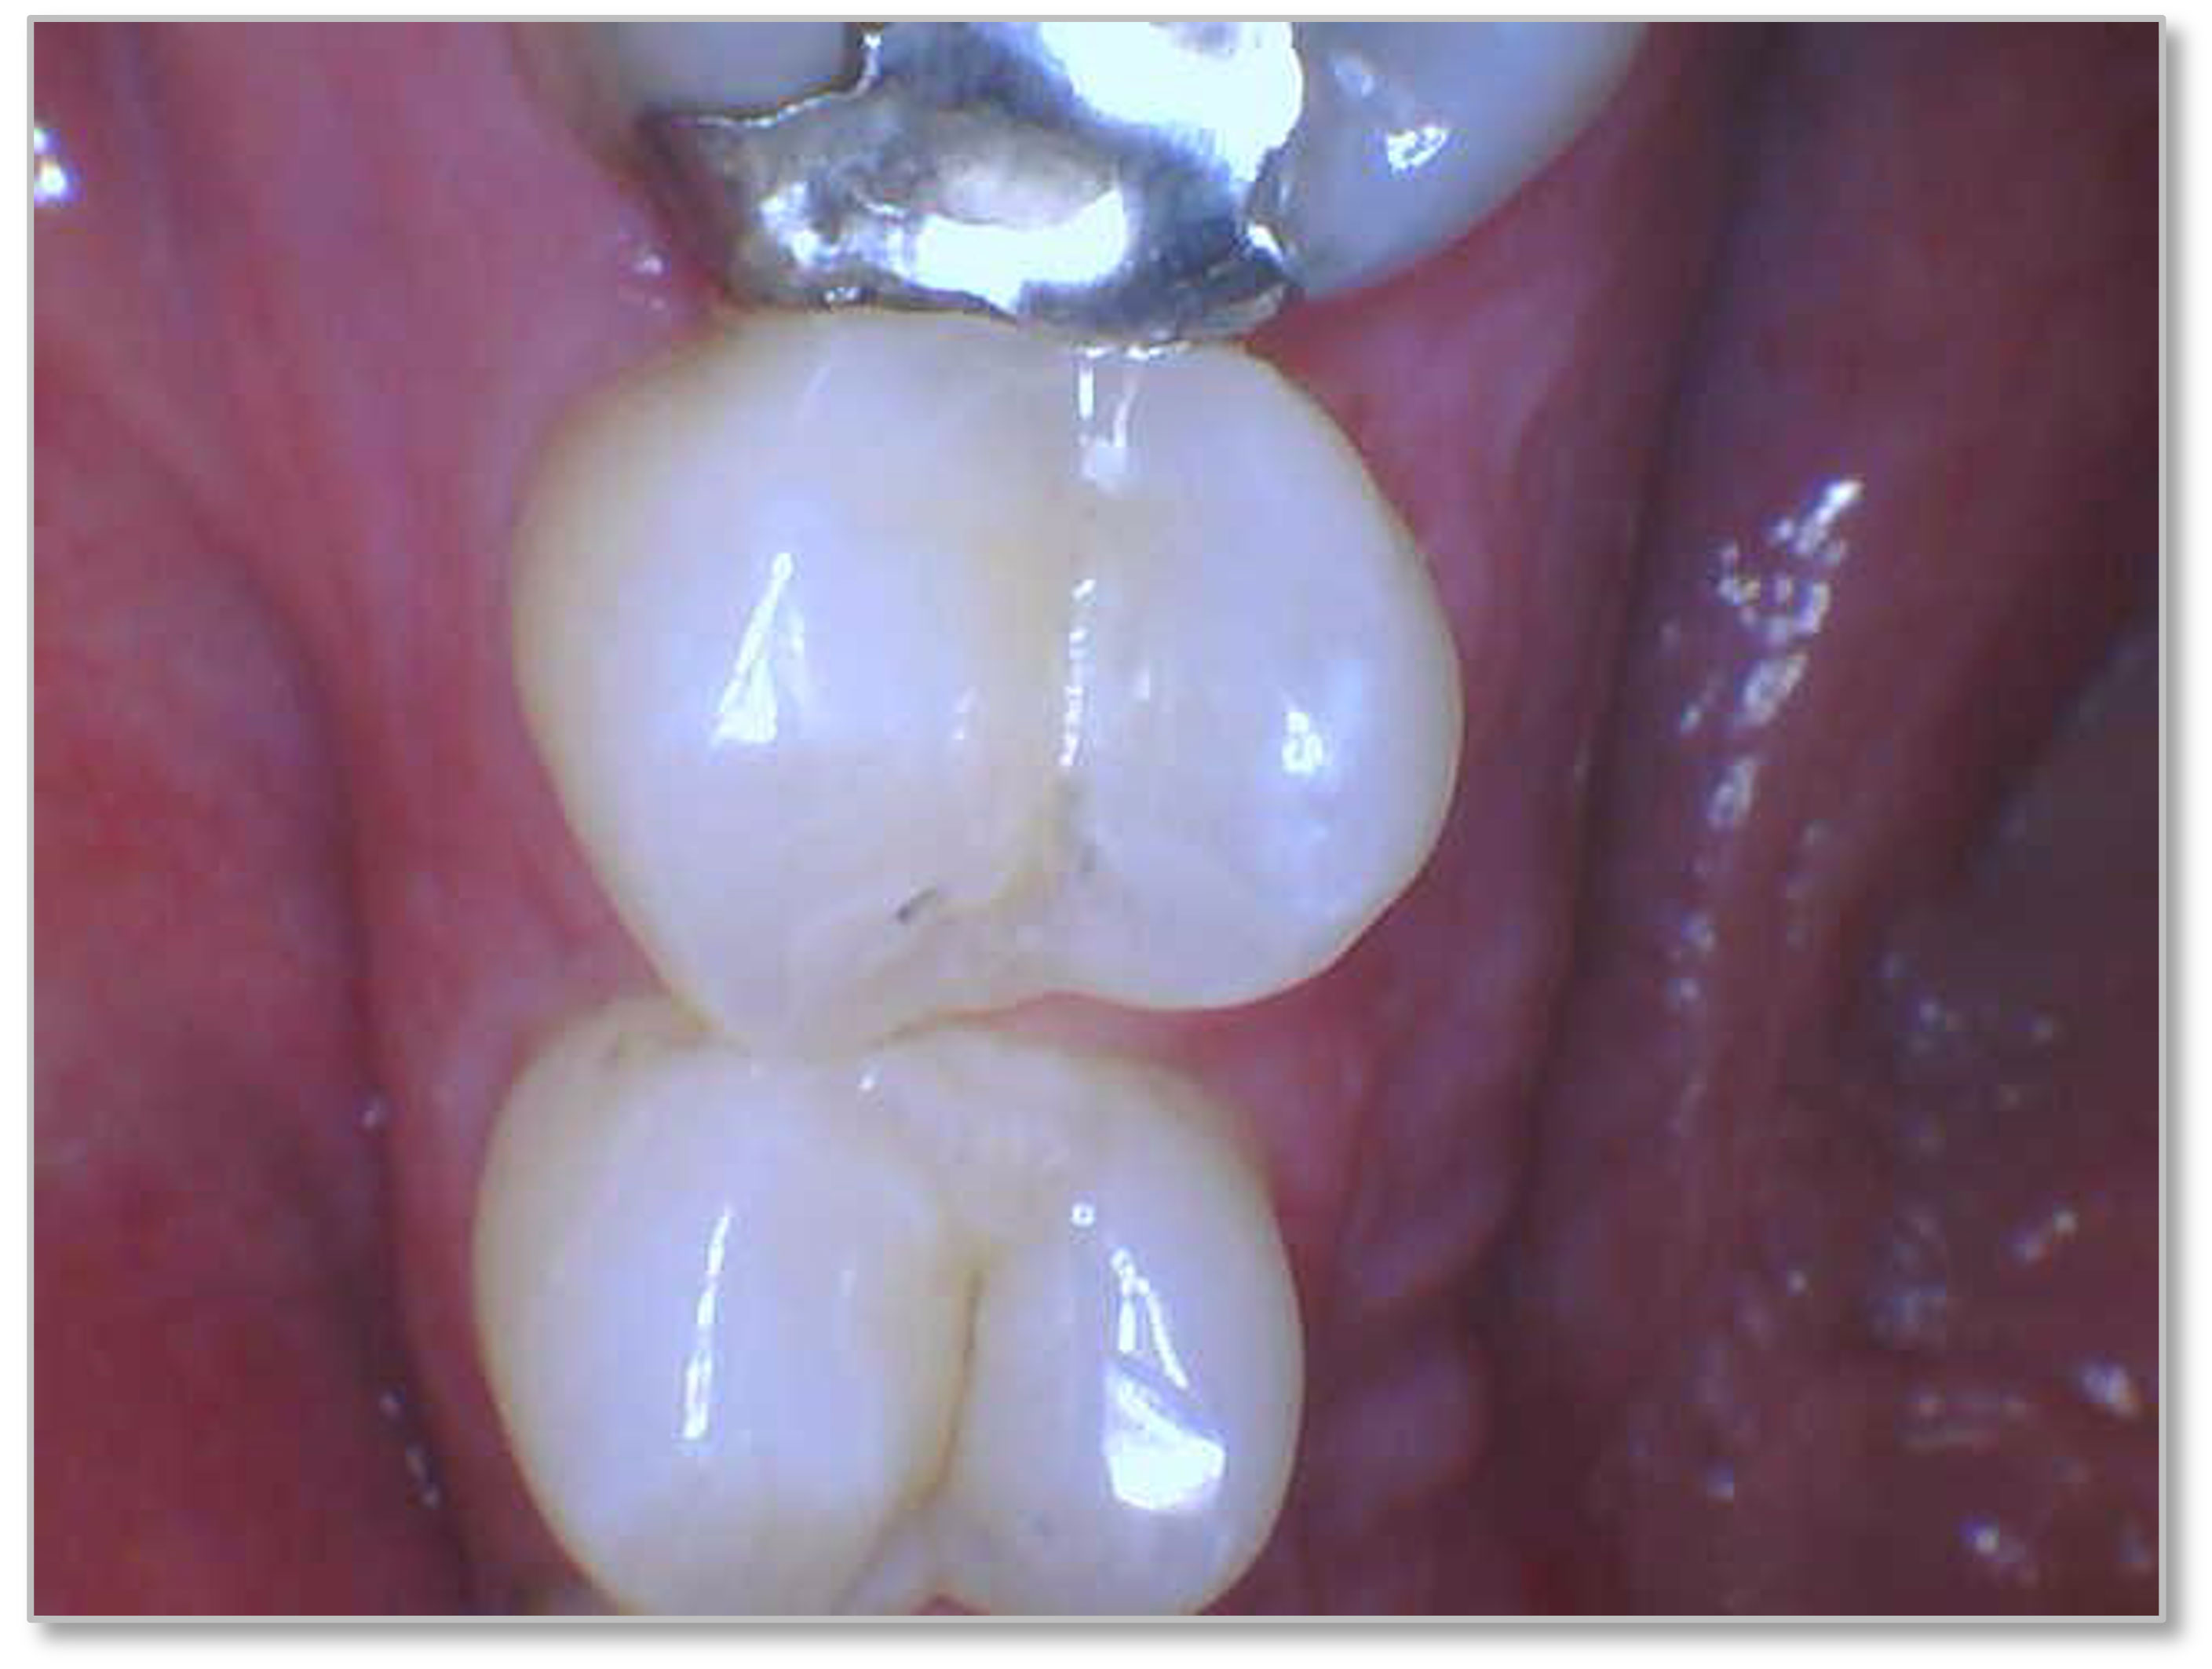

Figure 6a through Figure 6d show a procedure using a bulk fill packable as an interproximal Class 2, without using a bulk fill flow and not done with the snowplow technique to see how well the composite adapted to the margin. A light curable resin-modified calcium silicate liner (Bisco TheraCal LC) was used to perform an indirect pulp cap. A packable bulk fill composite was applied as a single increment layer to successfully restore the tooth. The material (Kerr SimpliShade Bulk Fill Packable) provided good adaptation to the tooth without gaps or polymerization stress lines and demonstrated great polishability and blendability. The patient reported no post operative sensitivity or discomfort in the 9 months after the restoration was performed. Sensitivity can be a concern if a composite is subjected to too much polymerization shrinkage.

Fig 6d. A procedure using a bulk fill packable as an interproximal Class 2, without using a bulk fill flow and not done with the

snowplow technique. A light curable resin-modified calcium silicate liner (Bisco TheraCal LC) was used to perform an indirect pulp cap. A

packable bulk fill composite was applied as a single increment layer. The material (Kerr SimpliShade Bulk Fill Packable) was used to provide

good adaptation to the tooth without gaps or polymerization stress lines and demonstrated great polishability and blendability.